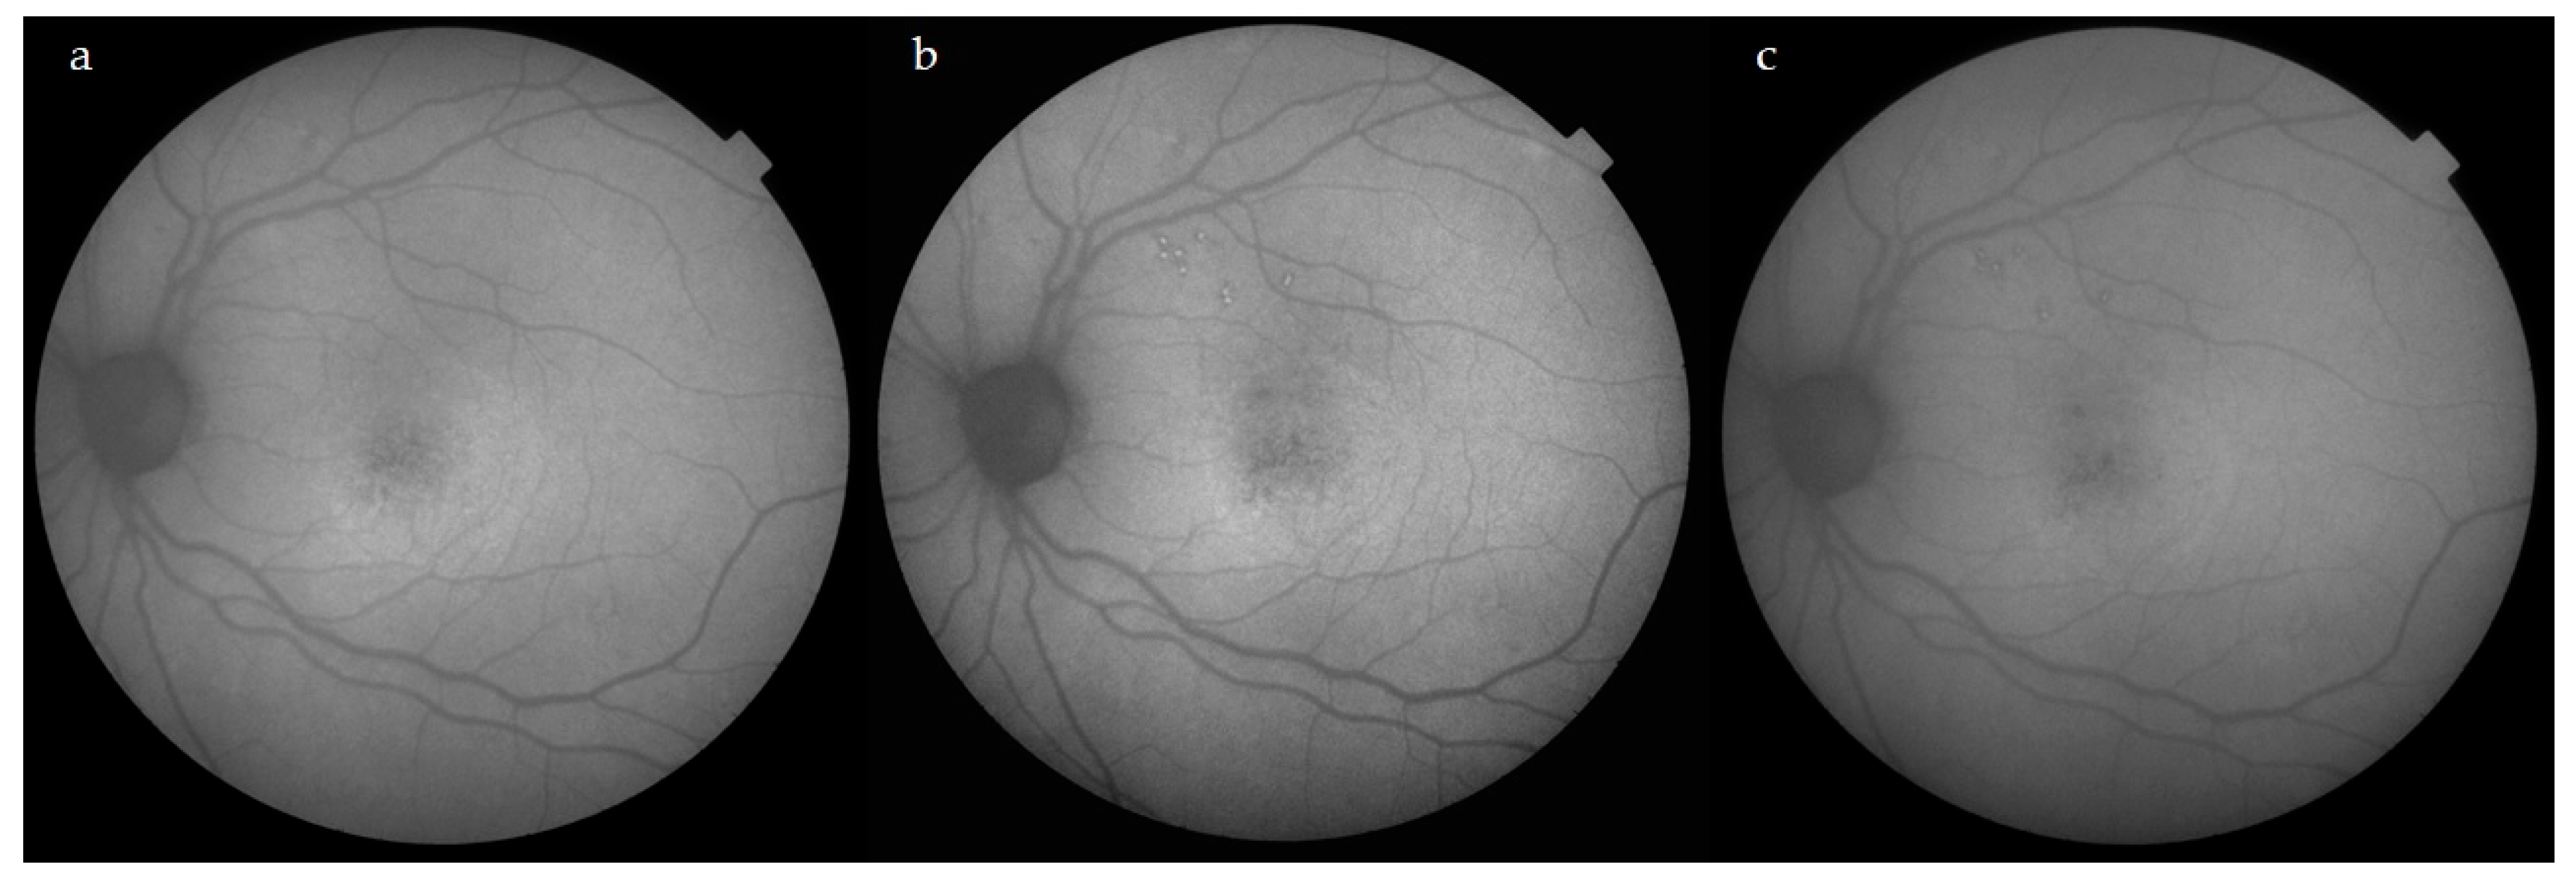

3.1. Subretinal Fluid (SRF)